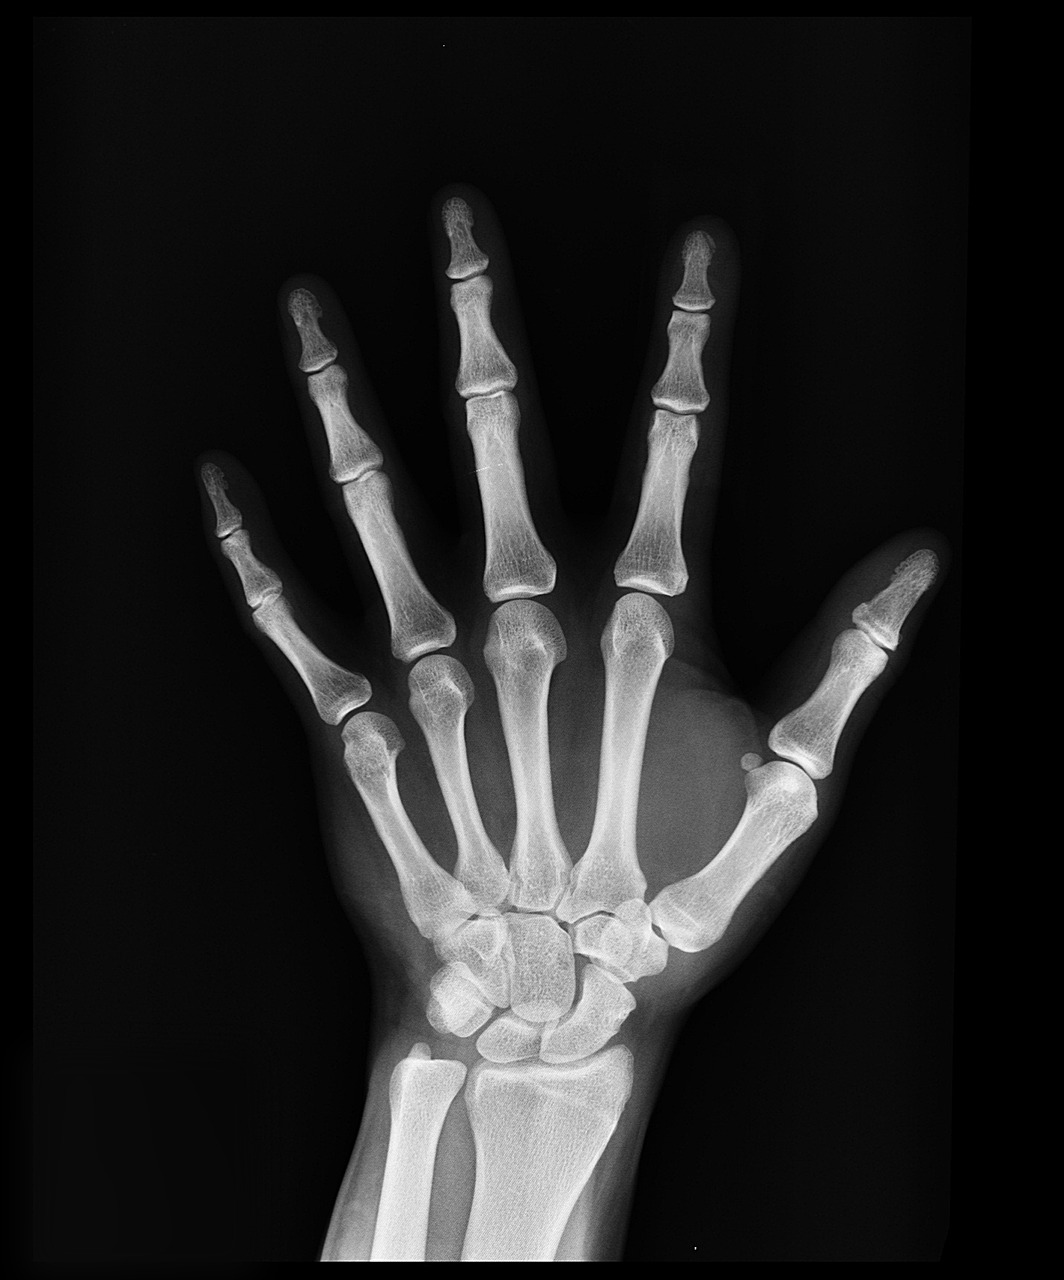

- 흉부 X-ray

폐결핵 등 호흡기 질환을 확인합니다. 이는 공기를 통해 전파될 수 있는 질병 예방을 위한 필수 검사입니다.